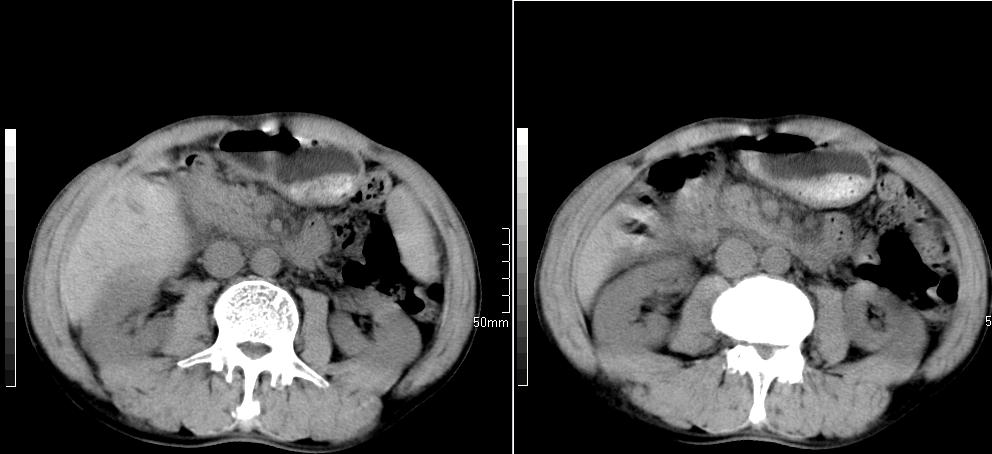

标题: CT26769:男,58岁,腹胀、腹部不适一年余 [打印本页]

标题: CT26769:男,58岁,腹胀、腹部不适一年余

肠系膜脂膜炎,胆囊炎,脾大。建议结合临床。鉴别:慢性胰腺炎并假囊肿形成。

1 慢性胰腺炎并假囊肿形成。2 慢性胆囊炎并累及肝边缘!

1)考虑慢性胰腺炎并假性囊肿形成。2) 慢性胆囊炎。3)肝内胆管扩张。

1肝内胆管扩张,性质待定,2慢性胰腺炎胰管扩张,胰腺颈部假囊肿,3肝左叶低密度为小囊肿,4胆囊炎。